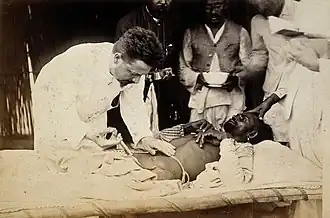

Plague patient being injected by a doctor in 1897, British Raj India | |